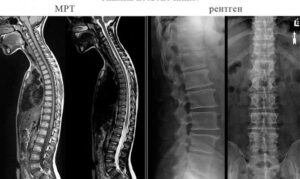

Что выбрать рентген или МРТ при обследовании позвоночника

В структуре заболеваний опорно-двигательного аппарата (МСД) заболевания позвоночника занимают ведущее место. Дегенеративно-дистрофические изменения выявляются у 85% людей в возрасте 15-50 лет. Многообразие форм, течения и риска развития осложнений требует тщательной детальной диагностики. По мере увеличения частоты выявления деструктивных процессов в костных структурах выбор вариантов обследования становится важным. Клиническая медицина предлагает ряд диагностических методов, требуются рентген …